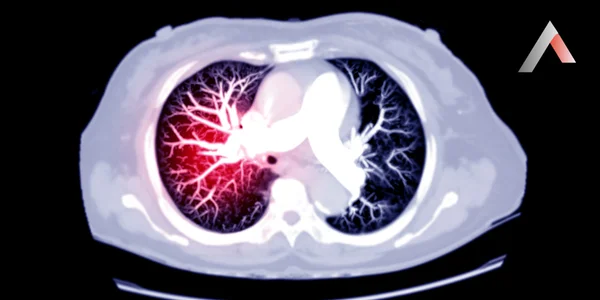

Pulmoner emboli (PE), akciğerlerdeki bir veya daha fazla atardamarın, genellikle bacaklardaki derin ven trombozundan (DVT) kaynaklanan bir kan pıhtısı tarafından tıkanmasıdır. Bu pıhtı, kan akışını engelleyerek akciğer dokusuna zarar verebilir ve hatta ölüme yol açabilir.

Pulmoner_Emboli_Nedir_e6adb41c.webp

Pulmoner Emboli Belirtileri

PE belirtileri kişiden kişiye değişebilir ve pıhtının boyutuna ve yerine bağlıdır. En sık görülen belirtiler şunlardır: